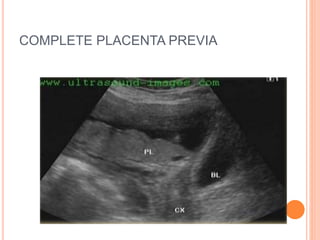

COMPLETE PLACENTA PREVIA